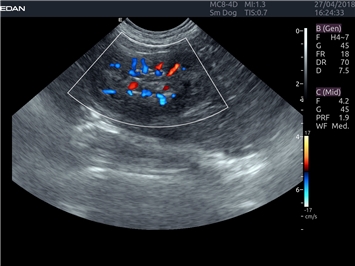

Трехмерная реконструкция ЦДК:

Да

Объемное сканирование:

Энергетический допплер:

Цветовой допплер: